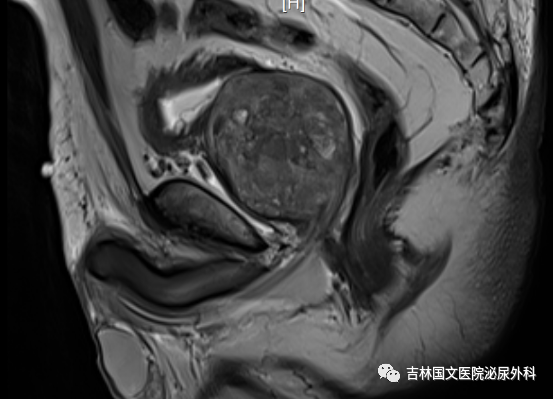

入院后行相關(guān)檢查,發(fā)現(xiàn)患者前列腺增生巨大,因治療延誤,已導(dǎo)致前列腺并發(fā)癥,出現(xiàn)膀胱功能受損,雙腎輕度積水。同時(shí)發(fā)現(xiàn)有腦梗死、雙肺支氣管炎、肺氣腫等基礎(chǔ)疾病,請(qǐng)相關(guān)科室會(huì)診,積極調(diào)整,改善身體素質(zhì)。同時(shí)明確向家屬告知手術(shù)風(fēng)險(xiǎn),手術(shù)后果,取得家屬支持認(rèn)可。家屬全力配合。經(jīng)認(rèn)真準(zhǔn)備,

患者在椎管內(nèi)麻醉下行經(jīng)尿道前列腺電切術(shù)。術(shù)中見(jiàn)前列腺中葉側(cè)葉明顯增大,向膀胱突出,尿道前列腺部明顯延長(zhǎng),因前列腺阻擋,膀胱加強(qiáng)收縮,膀胱壁明顯增厚,形成特有“小房小梁”結(jié)構(gòu)。在麻醉科精心配合下,谷欣權(quán)教授、張寶主任給予認(rèn)真細(xì)致手術(shù),術(shù)中反復(fù)止血,術(shù)后出血少,未輸血。術(shù)后認(rèn)真看護(hù),未出現(xiàn)腦梗死肢體功能障礙,未出現(xiàn)呼吸功能衰竭、心功能不全等常見(jiàn)并發(fā)癥。拔出尿管,患者排尿通暢,如開(kāi)閘洪水,一瀉千里,老人露出久違笑容,家屬也非常開(kāi)心,壓在心中的石頭終于落了地。